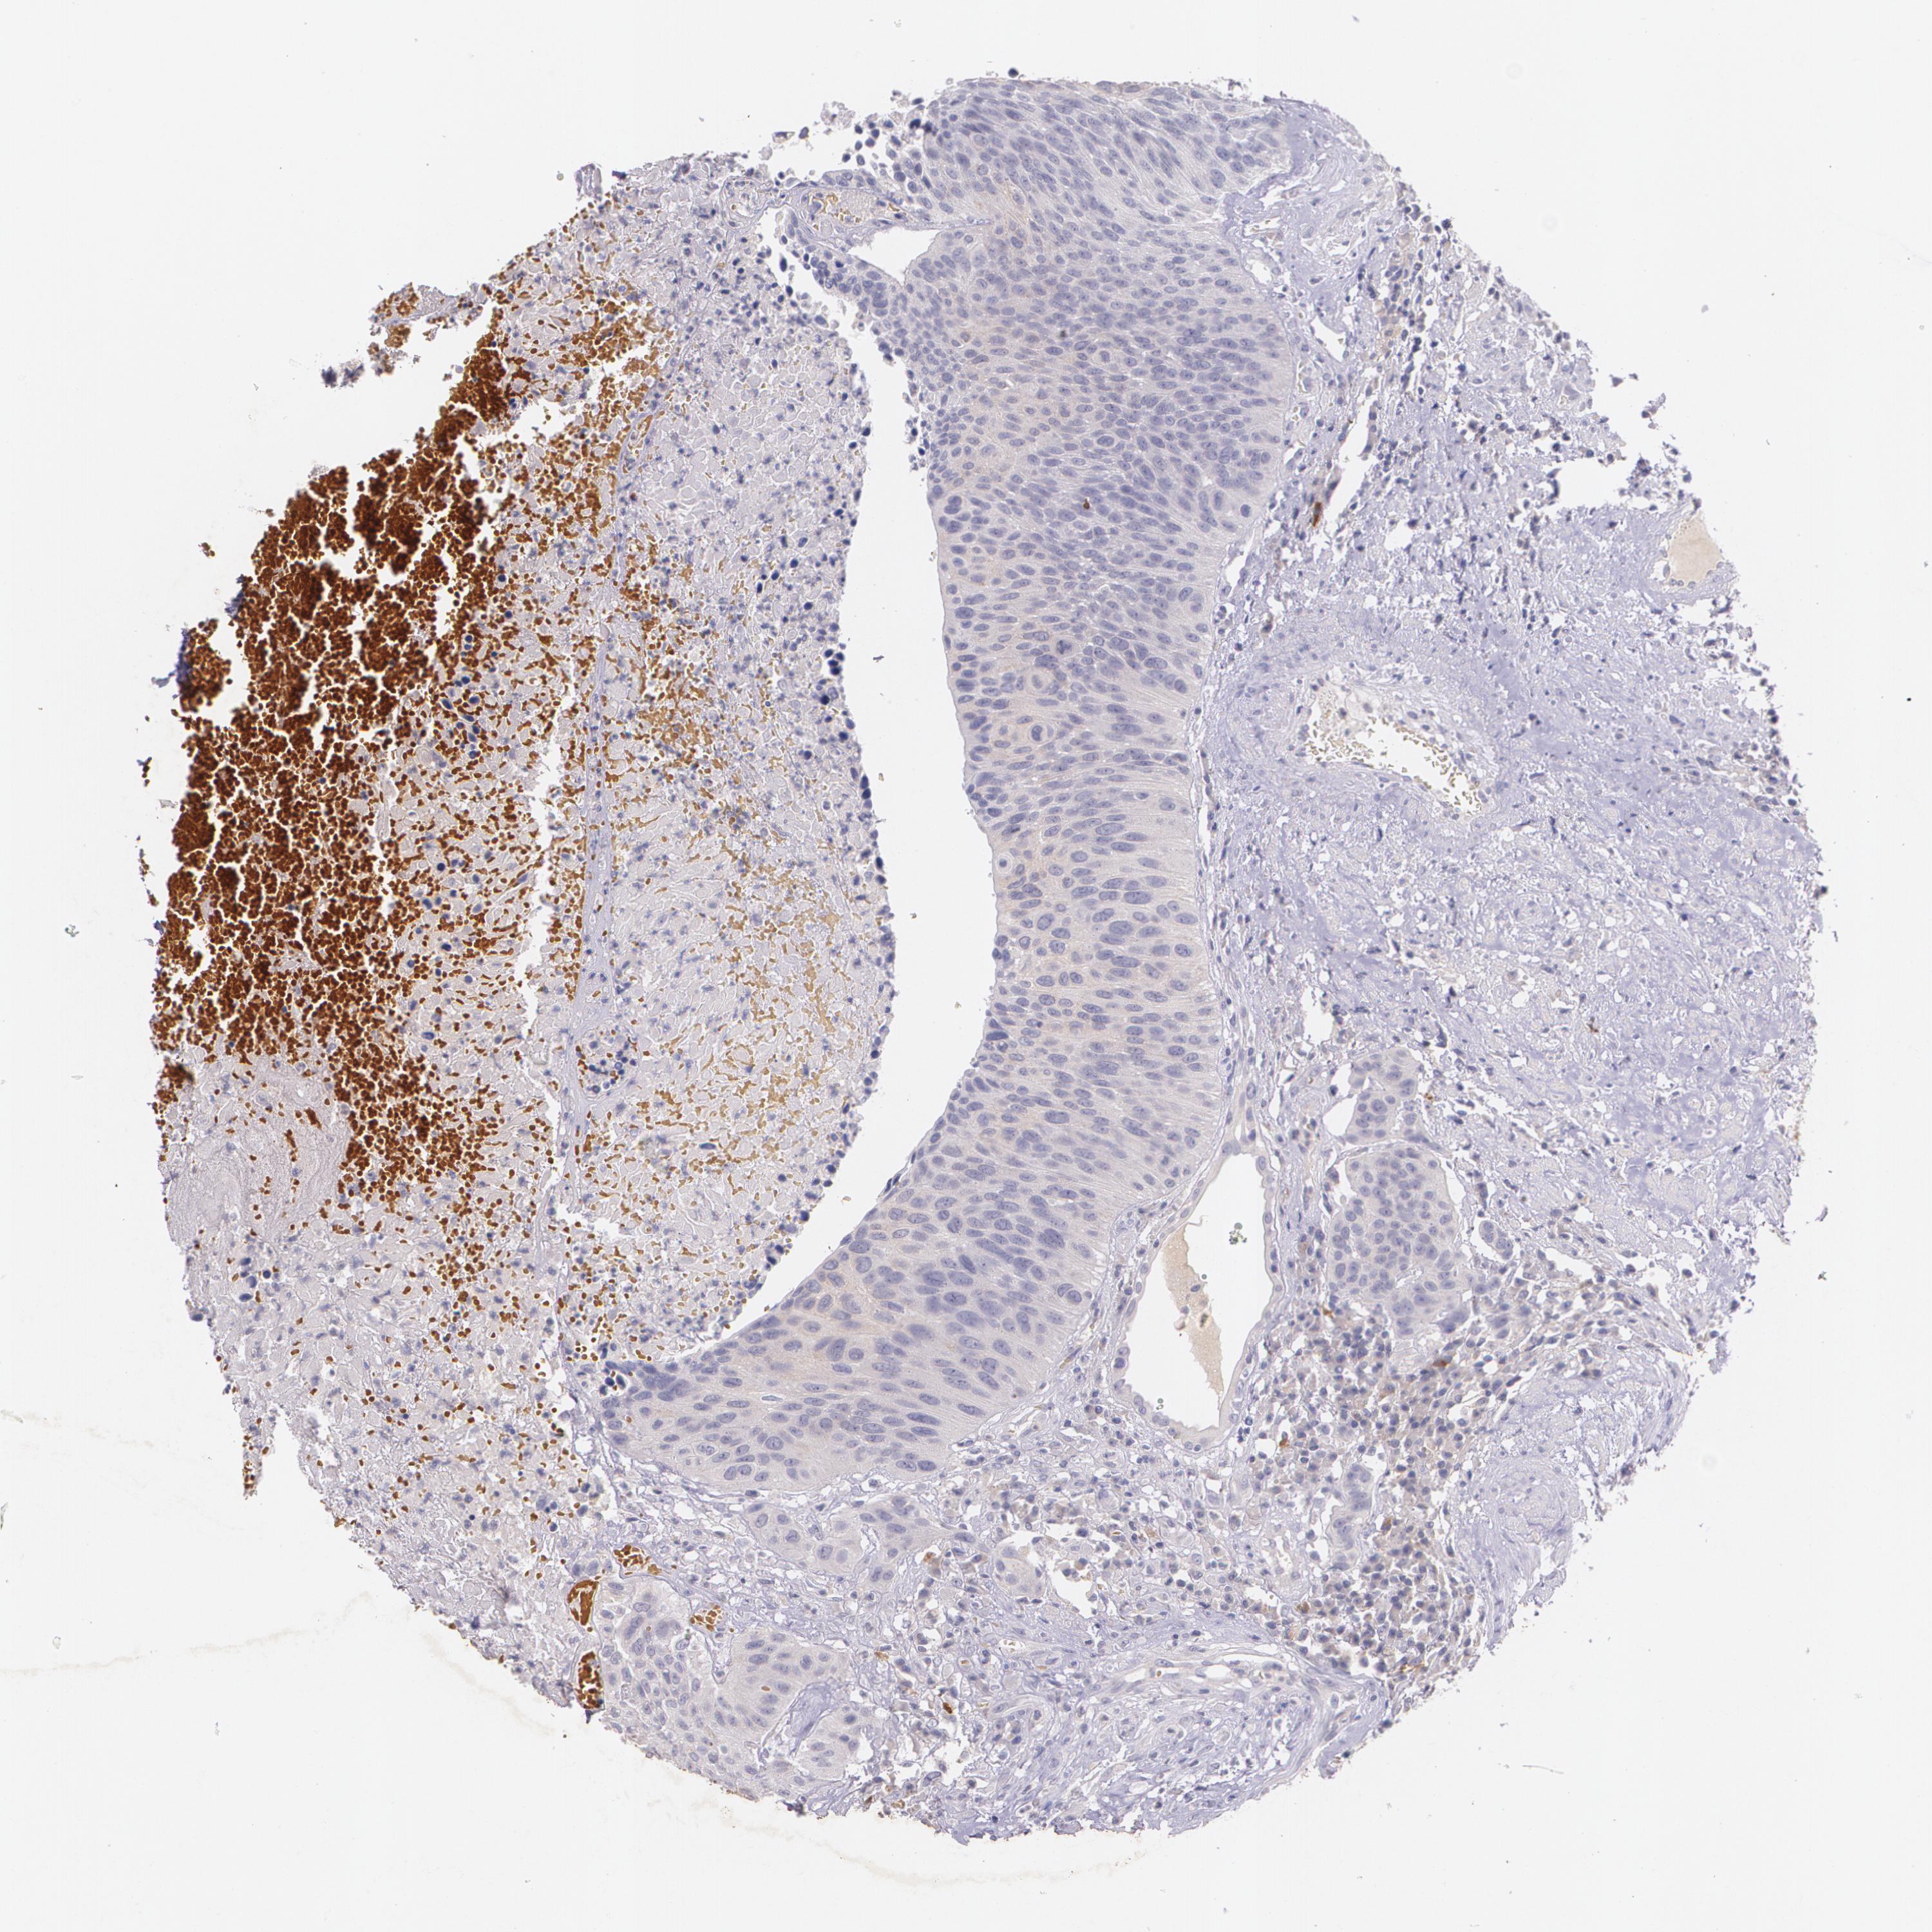

UROTHELIAL CANCER - Protein expressioni

A mouse-over function shows sample information and annotation data. Click on an image to view it in a full screen mode. Samples can be filtered based on level of antibody staining by selecting one or several of the following categories: high, medium, low and not detected. The assay and annotation is described here.

Note that samples used for immunohistochemistry by the Human Protein Atlas do not correspond to samples in the TCGA dataset.

Antibody stainingi

Antibody staining in the annotated cell types in the current human tissue is reported as not detected, low, medium, or high, based on conventional immunohistochemistry profiling in selected tissues. This score is based on the combination of the staining intensity and fraction of stained cells.

Each image is clickable and will lead to virtual microscopy that enables deeper exploration of all samples and also displays staining intensity scores, fraction scores and subcellular localization as well as patient and tissue information for each sample.

Antibody HPA002823

Antibody CAB002760

Staining

High

Medium

Low

Not detected

Intensity

Strong

Moderate

Weak

Negative

Quantity

>75%

75%-25%

<25%

None

Location

Nuclear

Cytoplasmic/membranous

Cytoplasmic/membranous,nuclear

Urothelial carcinoma, High grade

Urothelial carcinoma, Low grade

Adenocarcinoma, NOS